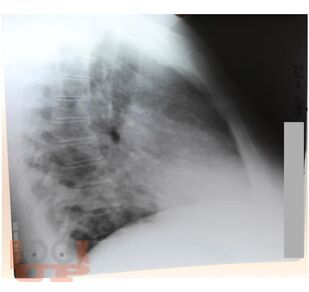

В учебном пособии рассматриваются вопросы терминологии, классификации, диагностики и лечения вирусных пневмоний, их осложнений и ассоциированных с ними патологических состояний. На основании собственного клинического опыта, рекомендаций доказательной медицины, новейшей отечественной и зарубежной литературы представлены материалы по тяжелым и осложненным формам гриппа, острому респираторному заболеванию (ОРЗ) и острой респираторно-вирусной инфекции (ОРВИ), острому бронхиту (ОБ), внебольничной пневмонии (ВП), острому респираторному дистресс-синдрому (ОРДС), сепсису, септическому шоку (СШ) и дыхательной недостаточности (ДН).